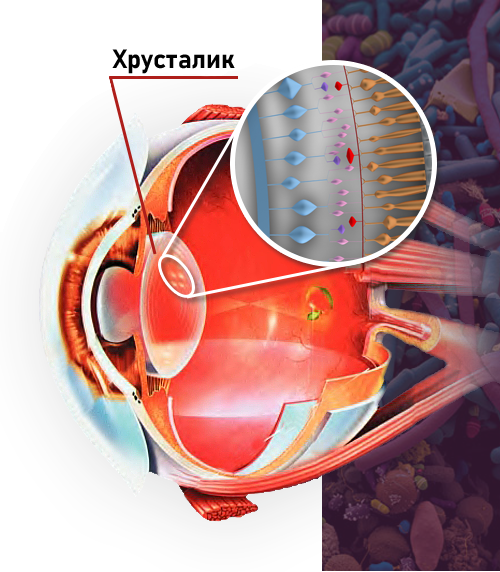

Основным условием нормального зрения — является эластичность хрусталика. К сожалению, эта способность ухудшается под воздействием многих факторов:

Главная причина плохого зрения

нарушение режима работы

глазных мышц!

- Мышечная система фокусирует глаза таким образом, чтобы получаемые изображения, проходящие через хрусталик, проецировались на сетчатку.

- Дисбаланс в мышцах может вызвать недостаточное или чрезмерное сжатие глазного яблока.

- Хрусталик деформируется, резкость зрения нарушается, изображение становится нечетким.